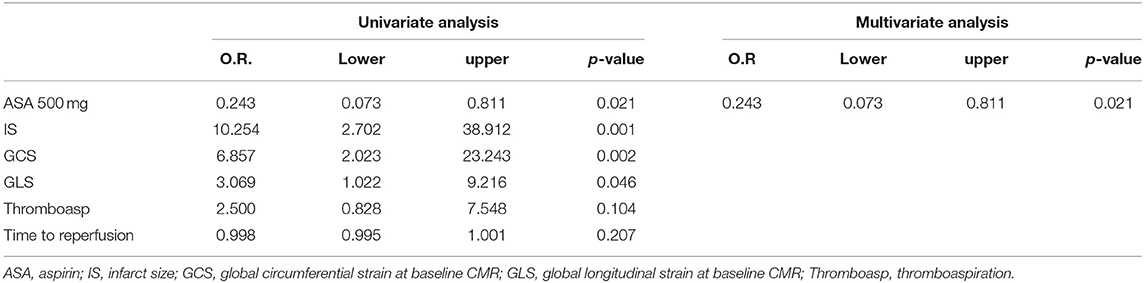

At ROC curve analysis (Figure 3), AAR, IS, MVO, GLS, and GCS values, measured at baseline CMR, showed significant sensitivity (Se) and specificity (Sp) to detect adverse remodeling at FU-CMR (AAR AUC 0.684, 95% CI 0.563–0.789, p = 0.0040 Youden index J 0.3476 with Se: 51% and Sp: 83%; LGE AUC 0.747, 95% CI 0.635–0.859, p < 0.001 Youden index J for LGE > 9.7% with Se: 93% and Sp: 40%; MVO AUC 0.637, 95% CI 0.514–0.747, p = 0.0405 Youden index J for MVO 0.39 gr with a Se: 42% and Sp: 97%; GLS AUC 0.639, 95% CI 0.521–0.745, p = 0.0306 Youden index J > −10.21 % with Se: 35% and Sp: 90%; GCS AUC 0.660 95% CI 0.543–0.764, p = 0.0138 Youden index J > −11.09 % with Se: 43% and Sp: 92%). In pairwise comparisons, there were no significant differences between the AUC of ROC curves of the measured CMR parameters by DeLong et al. (20) method (p > 0.05 for all). About infarct related artery, significantly worse GCS and GLS were observed in those having, as the culprit lesion, the left anterior descending artery (LAD) compared to circumphlex (LCX) and right coronary arteries (RCA) (GCS values in LAD −13.0 ± 4 vs. −16.0 ± 3% in LCX vs. −15.1±3% in RCA, p = 0.014; GLS values −12 ± 4% in LAD vs. −16.1 ± 3% in LCX vs. −15.4 ± 2% in RCA, p < 0.001).

The stepwise multivariate logistic regression analysis was adjusted for IS, GCS, and GLS cut-offs and related to adverse remodeling. An ASA loading dose of 500 mg remained an inverse independent predictor of early adverse LV remodeling (Table 5). The Hosmer-Lemeshow test demonstrated good calibration of the logistic regression model (χ2 = 1.095, p = 0.955).

Our study confirmed the value of the strain analysis provided by CMR-FT in assessing the risk of LV early adverse remodeling, according to Bulluck's definition (7). In particular, we demonstrated that cut-offs of −11.09% for GCS and −10.21 for GLS, measured at baseline CMR, are highly specific in predicting LV adverse remodeling whereas those parameters do not differ between patients with null and reverse remodeling. Although both strain CMR parameters have been used previously to predict adverse LV remodeling (11, 12, 21), they have never been applied to these new categories (7). Furthermore, we retrospectively evaluated the effect of ASA dose before pPCI in STEMI patients for the first time, and described a positive effect of a loading dose of 500 mg on early LV remodeling.

In this study, we categorized the population using the three LV remodeling patterns based on Bulluck's definition (7), observing a similar percentage distribution (adverse remodeling 49 vs. 45%, reverse remodeling 28 vs. 29%, and null remodeling 19 vs. 23%). For CMR parameters, the adverse remodeling group showed greater AAR, IS, and MVO at baseline CMR and greater IS at FU-CMR, as already reported (7). Otherwise, no differences in IS and MVO between reverse and null remodeling groups were found in our study. Notably, there were no differences in salvage myocardium extent among the three groups. Although IS and MVO are known predictors of adverse remodeling (7), the relationship between them and myocardial recovery is still an open issue (6, 7). Moreover, at FU-CMR, the adverse remodeling group showed lower LVEF, LV-RI, and greater IS, as compared to the other two groups. Regarding FT-CMR strain analysis, the adverse remodeling group showed worse GCS and GLS values at baseline and FU-CMR (Figure 5), if compared to reverse and null remodeling categories as one. Various studies investigated the value of FT-CMR features in predicting adverse remodeling (11, 12, 22), using different cut-off values and follow-up periods. For the definition of adverse LV remodeling, we considered LVEDV and/or an LVESV delta change of 12%, which is lower than most reports, and 6 months for follow-up, longer if compared to other studies, mostly around 3/4 months. Thus, this issue may have induced a larger rate of adverse remodeling in our population (49%), as compared to other cohorts (17–24.4%) (11, 12, 22, 23). In the majority of studies, baseline GLS was the best predictor of adverse remodeling among all strain values (11, 22–24). In particular, Reindl et al. (22) reported significant differences in baseline strain values and infarct size/MVO percentage between no remodeling and remodeling groups, as observed in our cohort. Moreover, they showed that a GLS-value > −14% was the best independent predictor of 4 months LV adverse remodeling (LVEDV delta change of 10%) with an AUC of 0.610, which do not differ substantially from our GLS AUC value of 0.639 using LVEDV/LVESV delta change of 12%. In the retrospective study of Cha et al. (11), at ROC curve analysis (AUC: 0.756, 95% CI = 0.636–0.887, p < 0.001), the GLS cut-off of −12.84% resulted in high sensitivity (Se: 85%) and low specificity (Sp: 61%) in predicting adverse remodeling at 6 months (LVEDV delta change of 20%), whereas in our study the optimal cut-off was lower (GLS > −10.21%), with lower sensitivity (Se: 35%) and higher specificity (Sp: 90%), likely reflecting the different criteria in classifying the remodeling groups. Interestingly, in our study GCS was the strongest predictor of adverse remodeling among the baseline strain values, as already reported by other authors (12, 25, 26). Holmes et al. (12) found that GCS was a superior predictor of LV adverse remodeling at 3 months follow-up than MVO, GLS, and GRS, although they considered a cohort of both STEMI and non-STEMI patients (12), differently from our population of STEMI only. Similarly, Buss et al. demonstrated that GCS is useful in predicting preserved LV function at 6 months follow-up but they did not evaluate LV remodeling groups (25).

For the other CMR factors, we compared strain parameters and IS in predicting adverse remodeling, demonstrating high sensitivity for IS cut-off of 9.7% (Se: 93%), whereas the GCS and GLS may offer high specificity at the optimal cut-off values (Sp: 92 and 90%, respectively). These results support the evidence that both GCS and GLS values are both useful in the prognostic stratification of STEMI patients and should be interpreted in combination with other CMR parameters, to improve risk profiling and tailoring of therapies.

In our study, the protective effect of ASA high loading doses in preventing adverse LV remodeling was independent of IS and myocardial strain values at multivariate analysis. Nonetheless, if confirmed, these data could have a relevant clinical impact, with potential implications on the clinical course and prognosis of a large number of STEMI patients. Therefore, further pharmacological interventional clinical trials that are adequately powered and possibly multicenter in approach, with a larger population and longer follow-up, are required.